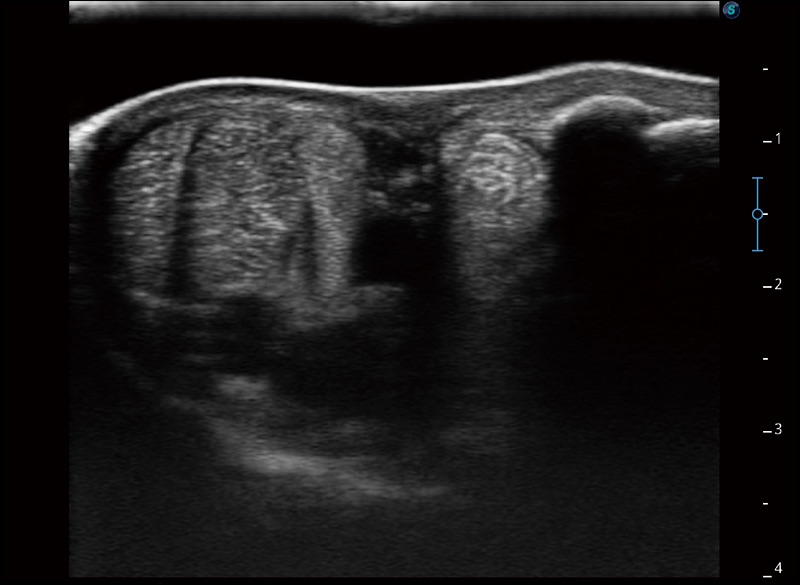

α1卓越的图像质量和便捷的工作流程,使每位宠物医生都能轻松扫查。其全面的兽用应用功能和紧凑型的结构设计,可以满足动物检查的多种需要。专业的预设检查模式和多领域测量软件包有助于为不同类型的动物提供检查, 让宠物医生能够出色的完成工作。

支持线阵和凸阵探头,一键操作即可获得更宽的图像视野

实时宽景成像

可实时观察感兴趣区域和病变位置